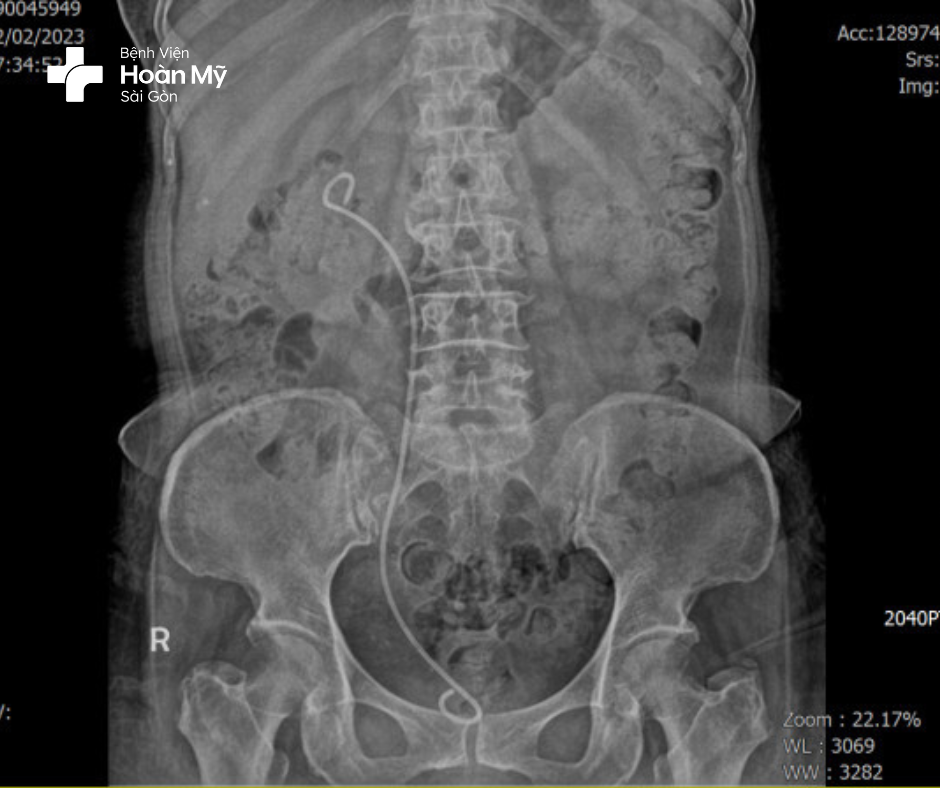

Hình 2: sau đặt sonde JJ